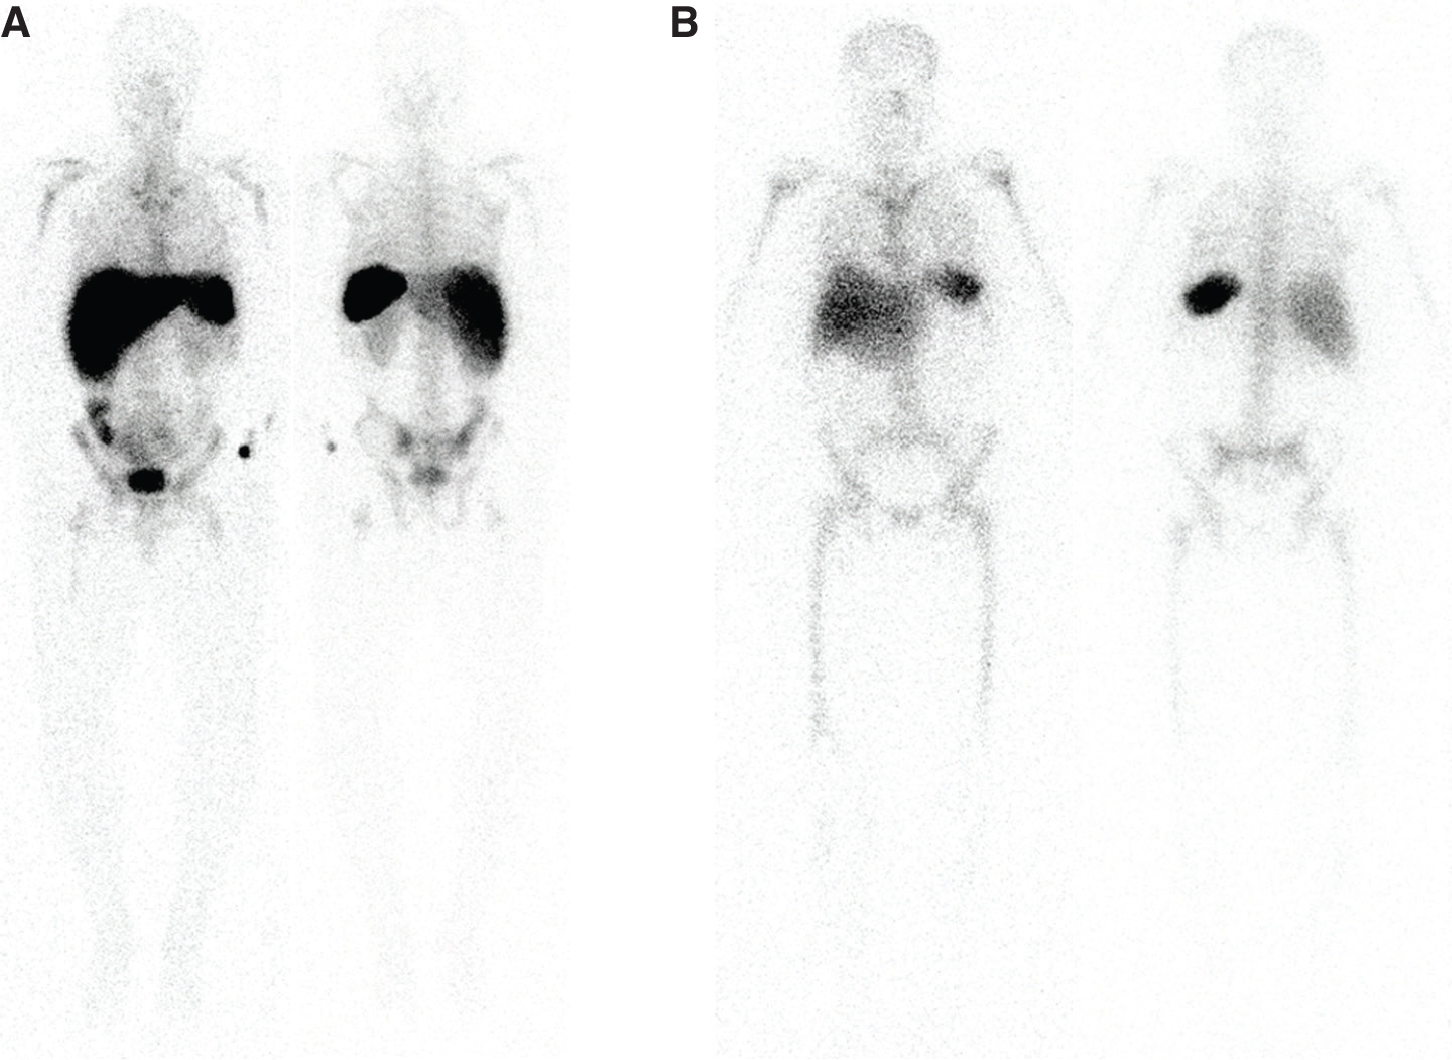

Fig 2

Figure 2 Normal biodistribution of radiolabeled leukocytes. A. 99mTc-HMPAO labeled leukocytes, and B. 111In-oxine labeled leukocytes. Note the lack of GI tract and urinary tract activity on the 111In-oxine labeled leukocytes.

This radiopharmaceutical also requires the patient’s own blood for labeling of autologous leukocytes with similar requirements for number of leukocytes and labeling process as 111In-Oxine labeled leukocytes. Similar care with delivery of the labeled leukocytes to the correct patient should be employed. 99mTc has a half-life of 6 hours and a photopeak of 140 keV, decaying by isomeric transition (7). 99mTc-HMPAO-labeled leukocytes will have normal activity in the bowel and urinary tract. Normal biodistribution is shown in Figure 2.